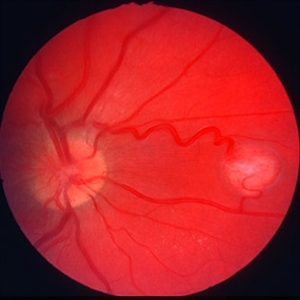

Retinal capillary hemangioma 2

Jan 11 2013 by Alex P. Hunyor, MD

Retinal capillary haemangioma, right inferior periphery, in a 20-year-old female with von Hippel-Lindau disease.

Condition/keywords: hemangioma, retinal capillary hemangioma, Von Hippel-Lindau